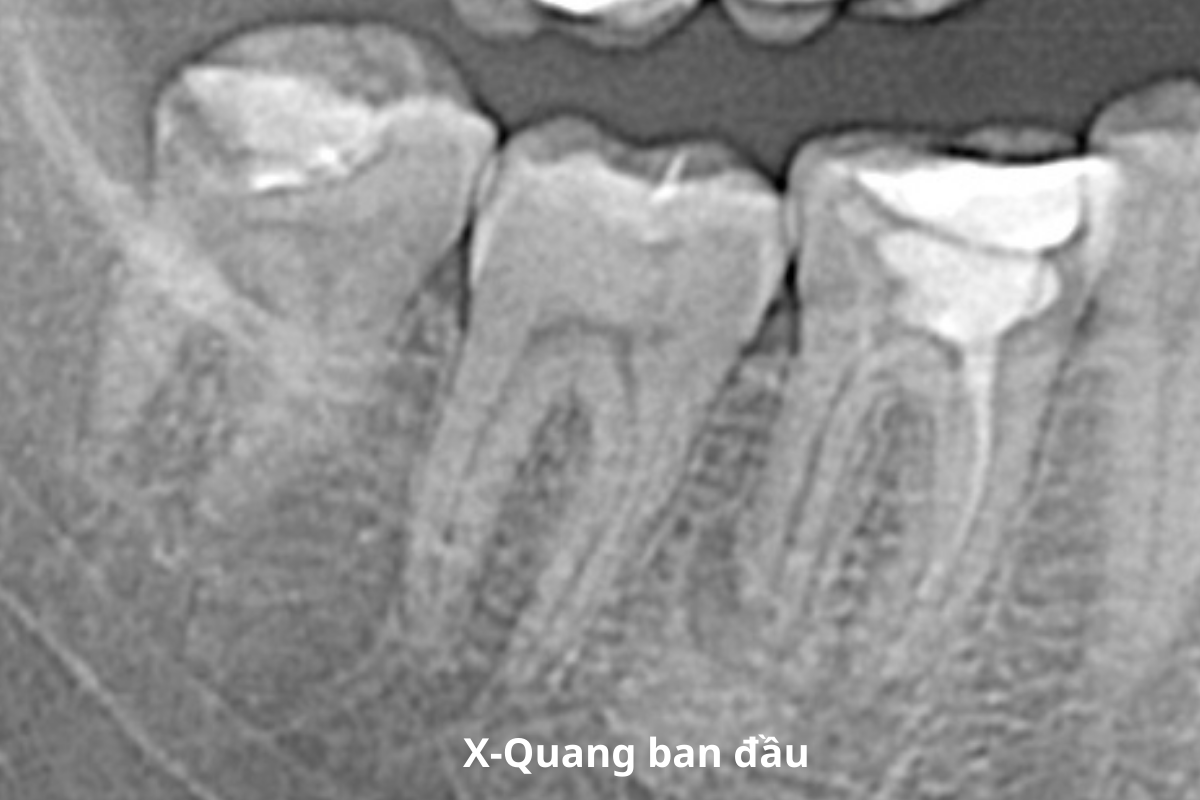

Tình trạng ban đầu

- Răng 46 đã nội nha (chữa tuỷ) hơn 10 năm

- X- quang: thuốc trong ống tủy đã tiêu/ thiếu, nhiễm trùng vùng chóp hai chân răng